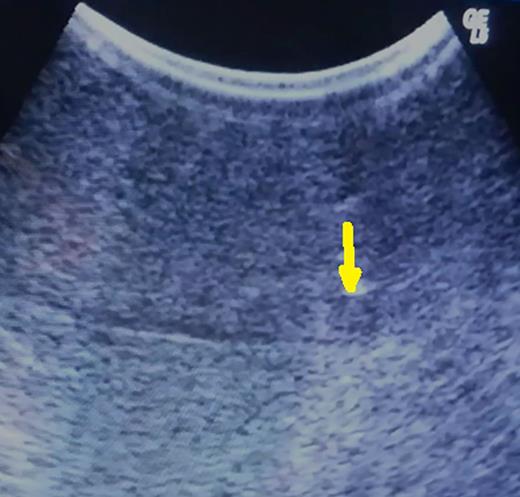

During the transection, close to the depth previously defined, intraoperative ultrasonography is repeated, and a well-defined area containing the tumor and methylene blue will be identifiable, despite the disruption of the hepatic parenchyma (Fig. 3). Resection is completed and specimen checked to confirm the presence of the lesion inside.

After parenchymal disruption, hyper-echoic lesion still clearly by ultrasonography (arrow).